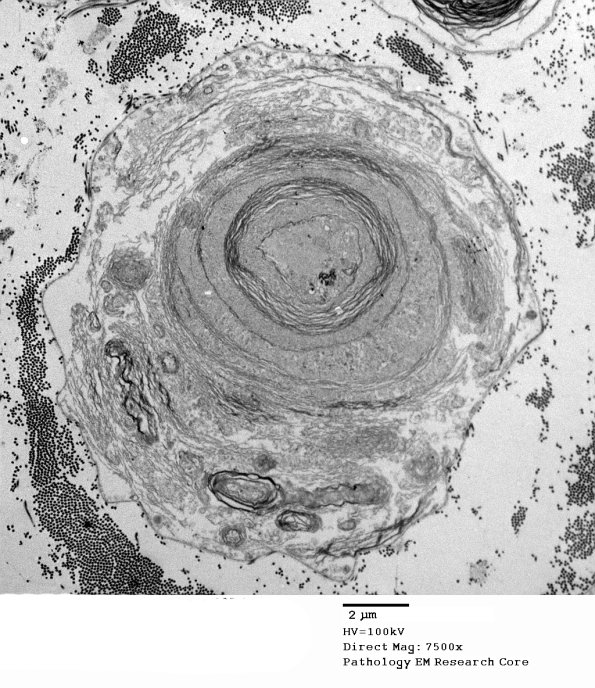

Washington University Experience | PERIPHERAL NEUROPATHY | 0 PNS ARTIFACTS | 19E1 Artifact, myelin EM 005 - Copy

19E1 Artifact, myelin EM 005 - Copy

19E1-3 The pattern varies from axon to axon in the same nerve. (electron micrograph)